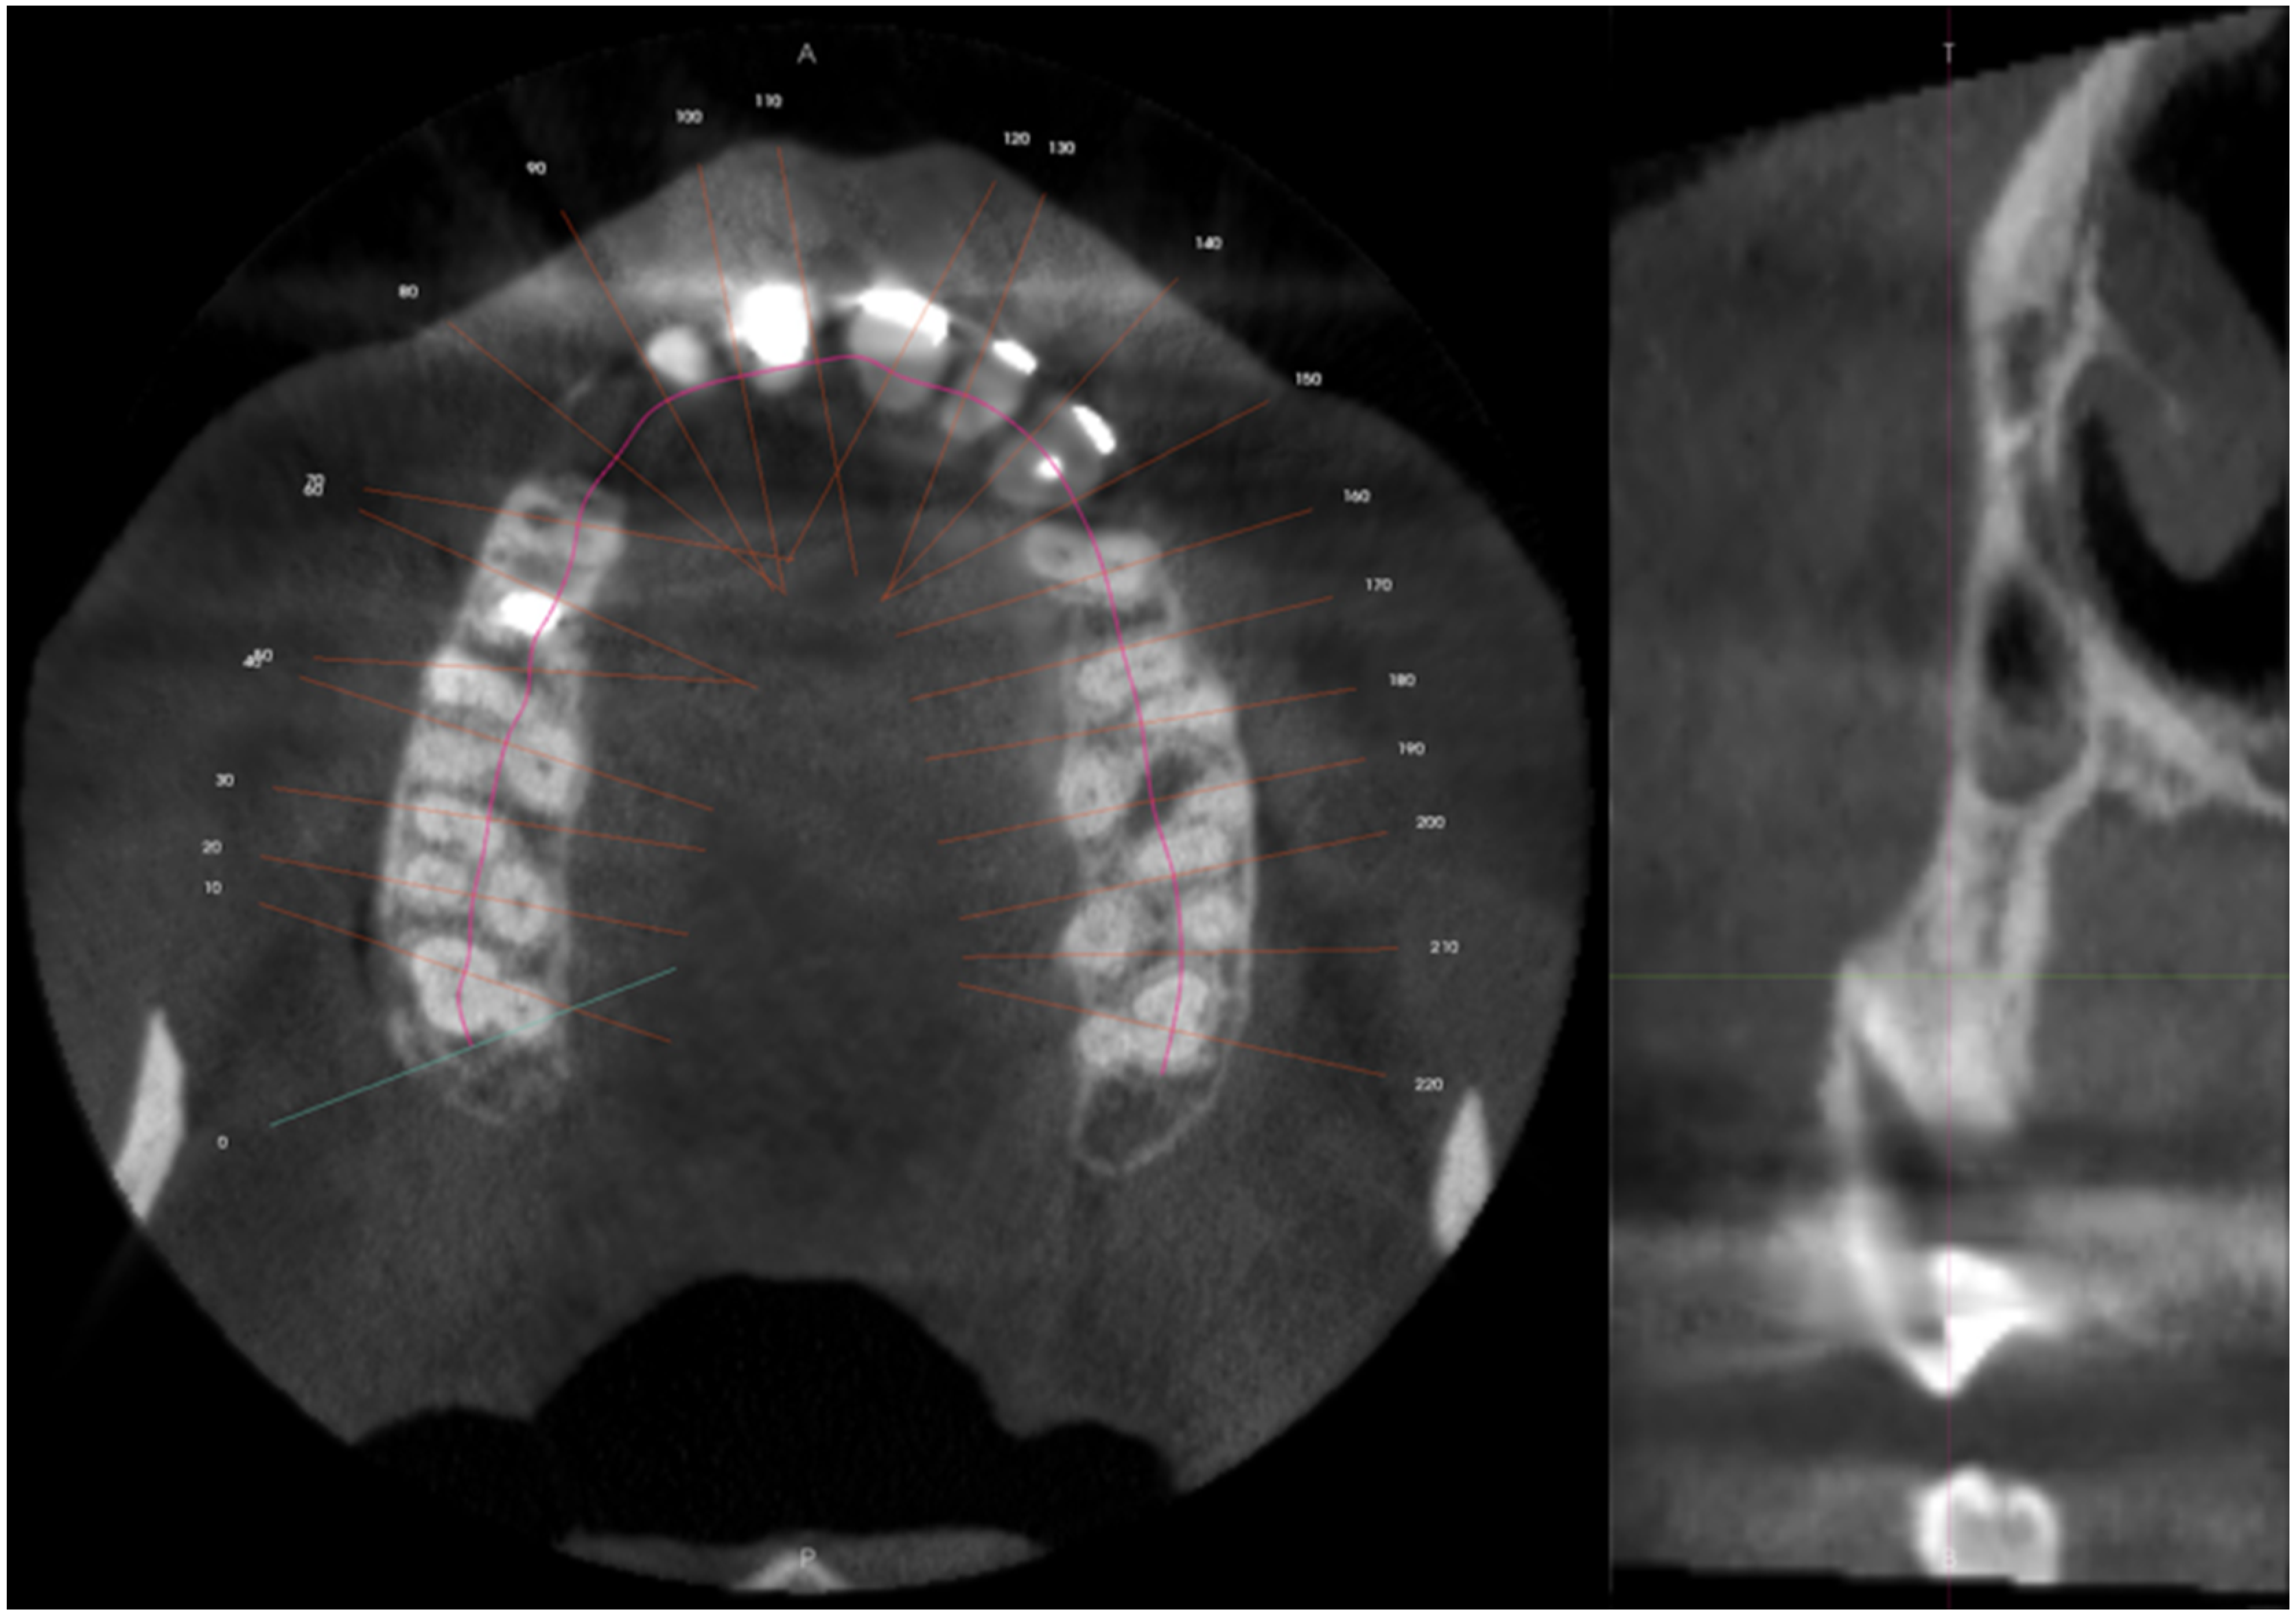

2.1. Report A

2.2. Report B

2.3. Report C

2.4. Report D